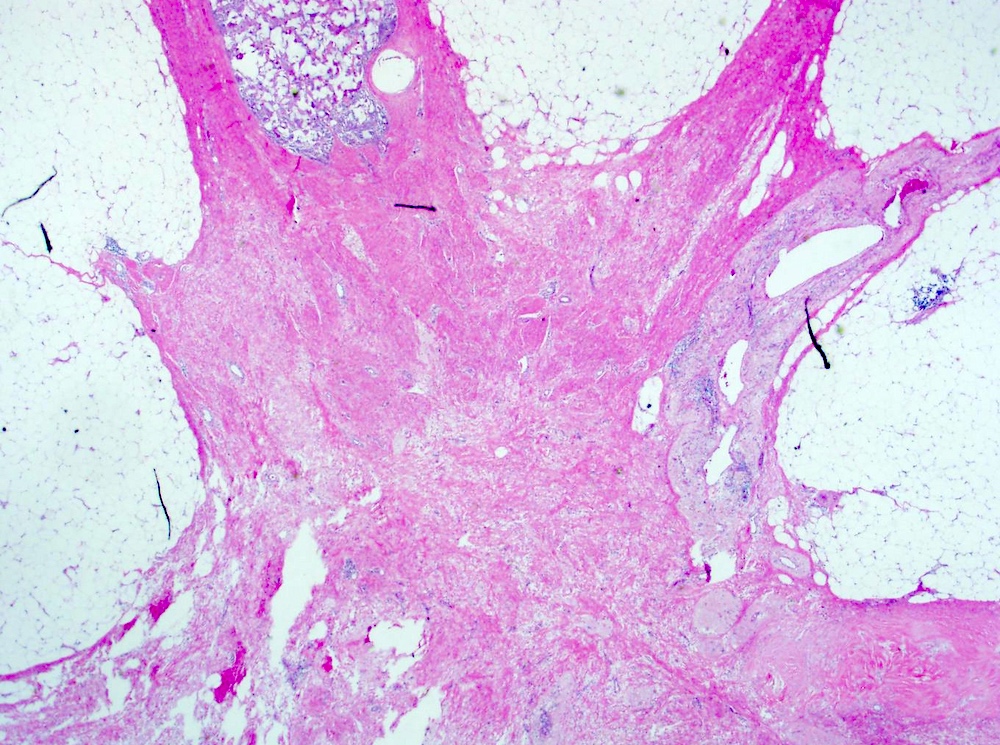

- Gross appearance of tumor may indicate degree of pathological response

- Tumors with poor response demonstrate a firm, gritty and spiculated appearance (i.e., no difference from typical untreated tumors)

- Response can be indicated by fibrosis or softening of the tumor bed (Mod Pathol 2015;28:1185)

- Tumors with partial response can be nodular, multifocal with and less well defined borders (Breast 2022;62:S25)

- In cases of complete response, the tumor bed may be soft and indistinguishable from normal breast tissue

- Tumor mapping with radiographs, photographs or drawings of the sectioned gross specimen is recommended (Mod Pathol 2015;28:1185)

Gross images

Microscopic (histologic) images

Contributed by Joshua J.X. Li, M.B.Ch.B., Gary M. Tse, M.B.B.S. and Emily S. Reisenbichler, M.D.